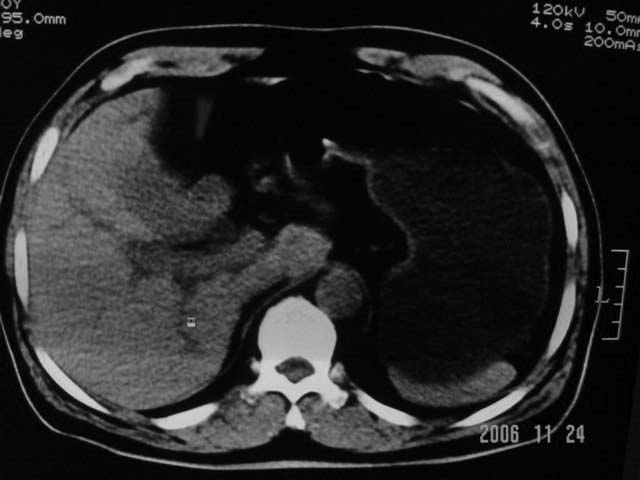

标题: CT5395:男、60岁,皮肤、巩膜黄染伴上腹部疼痛20天 [打印本页]

标题: CT5395:男、60岁,皮肤、巩膜黄染伴上腹部疼痛20天

劳烦各位老师看一下最后一幅箭头指的地方是不是胆总管结石.ct值约63hu.

感觉不是结石可能,与上一层面联系应该是门脉区影像,图像显示不佳,胆总管显示不清[特别是胰头以上段],目前影像只能说肝内外胆管扩张,胰管扩张,胆囊扩大。提示胆总管远端梗阻。可考虑肿瘤或结石所致

请结合临床及进一步检查。

胆总管内结节状高密度灶,边缘隐约可见低密度环绕,首先考虑结石伴肝内胆管扩张; 2、胆囊增大,胆囊炎

不过最好与超声结合或增强扫描

肝内外胆管及胰管均示有扩张,胆囊增大.提示胆总管远端梗阻,可考虑肿瘤或结石或肿瘤伴结石,建议强化扫描